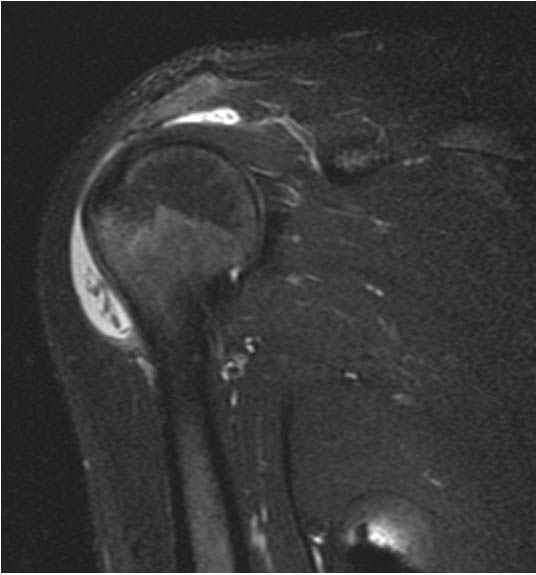

A, B) Yağ baskılı T2A koronal, C)Yağ baskılı T2 aksiyal, D, E) Yağ baskılı T2A oblik sagitalF) TSE T1A oblik sagital kesitlerde; subakromiosubdeltoid bursada efüzyon mevcut olup, efüzyon içinde pirinç tanesi cisimcikleri TZ ağırlıklı kesitlerde hipointens ve Tl ağırlıklı kesitlerde sıvıdan güçlükle ayrılacak şekilde hipointens olarak izlenmektedir.

(2). Olgumuzun ankilozan spondilit tanısı bulunmaktadır. Pirinç tanesi cisimciklerinin MR görünümü, T1 ve T2 ağırlıklı görüntülerde izo ya da hipointens olarak tanımlanmıştır.

(3) . Olgumuzda subakromiosubdeltoid bursada effüzyon mevcut olup, effüzyon içinde pirinç tanesi cisimcikleri T2 ağırlıklı kesitlerde hipointens ve T1 ağırlıklı kesitlerde sıvıdan güçlükle ayrılacak şekilde hipointens olarak izlenmektedir.